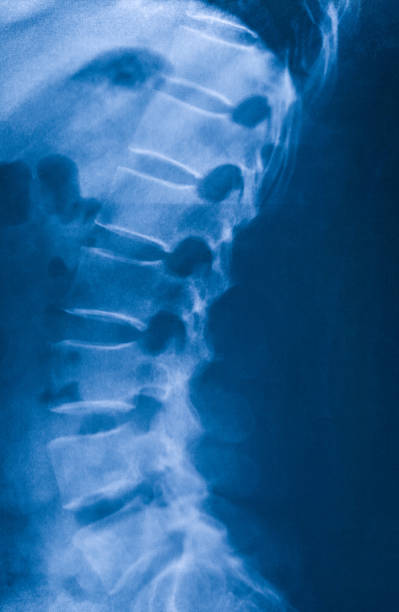

골반 통증 원인 두 번째는 천장관절증후군입니다. 천장관절 증후군 역시 허리디스크와 비슷한 통증으로 오인을 받을 수 있는데 천장관절 주변에 위치한 인대 손상, 관절의 불균형과 불안정성 대문에 허리와 엉덩이 주변으로 각종 통증이 생기는 질환을 의미합니다.

처장관절은 천골(엉치뼈), 장골(엉덩이뼈)가 만나는 부위로 외부 충격 혹은 골반이 힘을 주며 불편한 자세로 일어나거나 한쪽으로 체중이 쏠리는 잘못된 자세로 인하여 천장관절 주변으로 조직이나 인대 등에서 통증을 유발하는데 심할 경우 계단 오르내리는 것 자체도 어려워 질 수 있습니다.

허리디스크와의 구별은 허리디스크 환자는 아침에 일어날 때는 별다른 통증은 없으나 움직이면 통증이 심해지지만 천장관절증후군은 오히려 아침에 일어날 때 극심한 통증과 함게 기상하며 일상생활을 보내면서 증상이 완화되는 느낌이 난다는 것이 특징입니다.